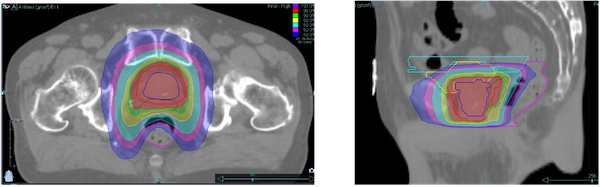

前立腺と直腸の間にハイドロゲルスペーサーを入れることにより、直腸の被ばく線量を低く抑えた治療が行えます。